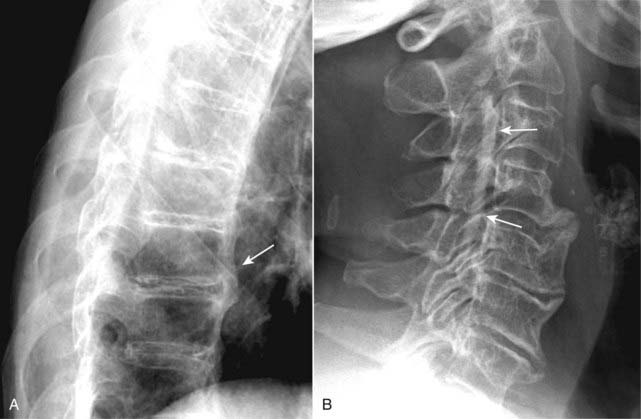

image With increasing age, the normally gelatinous nucleus pulposus becomes dehydrated and degenerates. This gradually leads to progressive loss of the height of the intervertebral disk space. At times, desiccation of the disk leads to release of nitrogen from tissues surrounding the disk resulting in the appearance of air density in the disk space called a vacuum-disk phenomenon. A vacuum-disk represents a late sign of a degenerated disk (Fig. 24-7).

image Degenerative disk disease on conventional radiographs:

There is disk space narrowing. There are also changes in the vertebral bodies themselves.

The endplates of contiguous vertebral bodies become eburnated or sclerotic. Small osteophytes are produced at the margins of the vertebral bodies at each disk space (see Fig. 24-7).

At the same time, there is typically degeneration of the outer annulus fibrosus. This leads to the production of larger marginal osteophytes at the endplates than those seen with degeneration of the nuclear material.

Figure 24-7 Degenerative disk disease.

With increasing age, there is progressive loss of the height of the intervertebral disk space. The endplates of contiguous vertebral bodies become sclerotic (solid black arrow), small osteophytes are produced at the margins of the vertebral bodies (solid white arrow), and there is desiccation of the disk with a vacuum-disk phenomenon (gas in the disk space) recognized by the air density in place of the disk seen at L5-S1 (dotted black arrow).